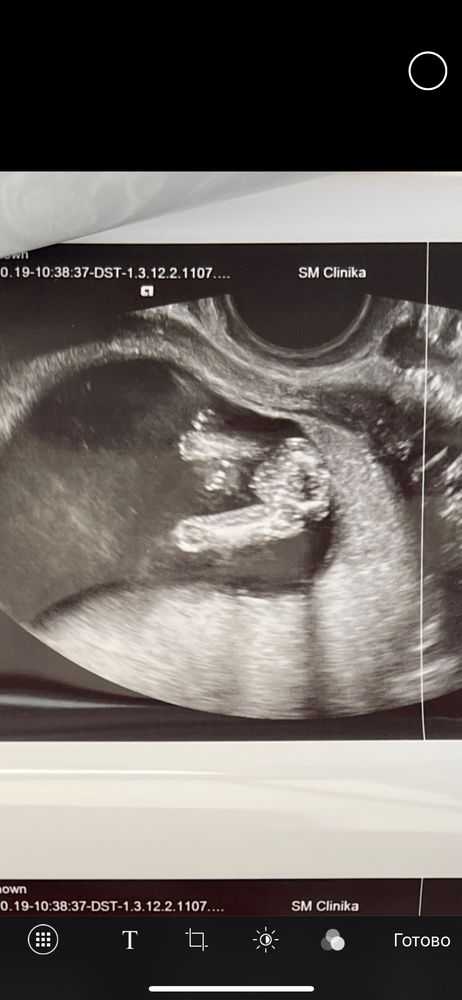

Софья, добрый день. Кого видите? Изображение

Polina Dyakova, к сожалению я по узи не понимаю🙈

Софья, сказали 95 % девочка❤️

Мне кажется девочка. Здесь столько было фоток с такого ракурса, у мальчиков между ног уже виднеется., но время покажет.

Кажется,девочка)